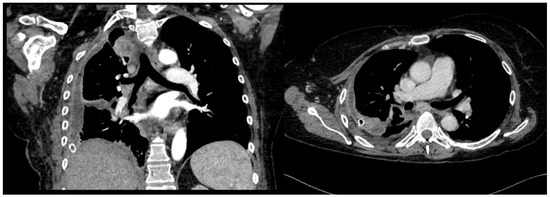

A 60-year-old Caucasian man was admitted to our hospital with a history of worsening pain at the base of the right hemithorax and feeling generally unwell for over one month. The patient’s past medical history included coronary heart disease, with a percutaneous coronary intervention in 2014. He smoked a half-pack of cigarettes per day for 40 years and had no history of respiratory disease. The CT chest scan showed a fluid collection in the medium–lower parts of the right hemithorax with thickened walls and contrast enhancement (Figure 5). This collection appeared in continuity with further smaller fluid collections with thickened walls, contrast enhancement, and confluence and caused the complete atelectasis of the middle and lower lobes and the partial atelectasis of the upper lobe, as well as middle and inferior lobar bronchus occlusion.

Figure 5. Chest CT scan of the mediastinal window in the coronal (A) and axial (B) plane, showing fluid collection in the medium–lower parts of the right hemithorax (maximum axial dimeters of 19 × 13 cm; craniocaudal extension of 16 cm) with thickened walls and contrast enhancement. There is also a complete atelectasis of middle and lower lobes and partial atelectasis of the upper lobe.